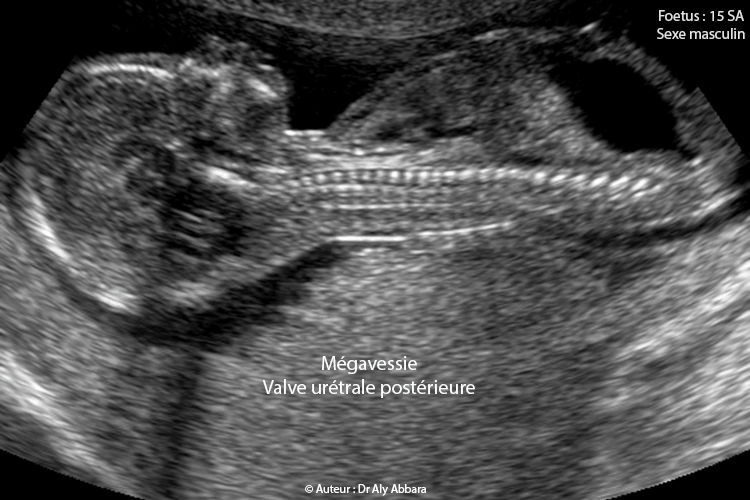

Mégavessie dans le cadre de la présence d'une valve de l'urètre postérieure - Foetus de 15 SA, du sexe masculin

Images échographiques animées montrant une mégavessie chez un foetus de 15 SA, du sexe masculin ; il s'agit d'une pathologie vésicale liée à la présence d'une valve urétrale postérieure qui se manifeste par la dilatation de la partie proximale de l'urètre postérieur ; ce dernière prend l'aspect du trou de la serrure.

L'aspect échographique typique est une dilatation de la vessie et la partie proximale de l'urètre postérieur donnant le signe du "trou de la serrure - keyhole", mais l’atrésie de l'urètre peut donner dans certains cas le même signe. La distension de la vessie est de volume variable selon le degré de la sévérité de l'obstruction urétrale et dans certains cas on peut observer la présence de vessie de lutte, de grand volume et à paroi épaisse avec des diverticules au premier temps, puis en deuxième temps, vessie volumineuse hypotonique à paroi fine.